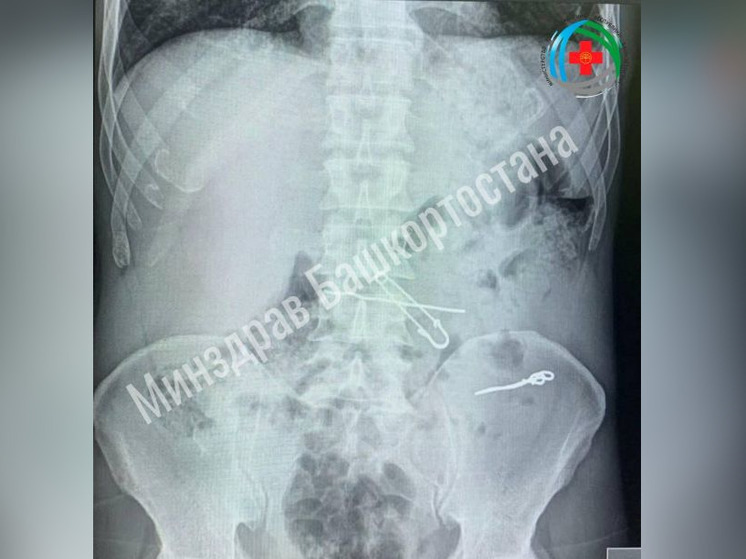

В Уфе врачи больницы скорой медицинской помощи спасли жизнь мужчине, который проглотил проволоку и скрепки. Об этом сообщил в соцсетях министр здравоохранения Айрат Рахматуллин.

Пациент поступил в медучреждение с болями в животе. Исследования показали наличие в его организме инородных предметов длиной 47,62 и 90 мм. Хирурги провели операцию, удалив из кишечника проволоку и скрепку, а из желудка – булавку и проволоку. Пациент пошел на поправку и вскоре отправился для восстановления домой.